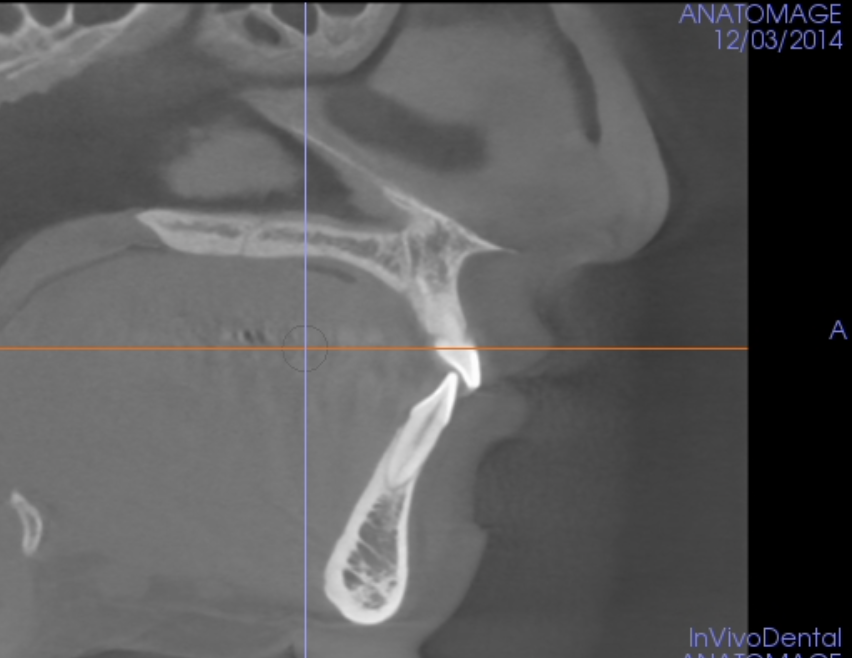

4

Q

What view?

A

Sagittal